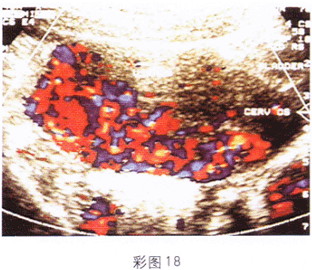

女性,36歲,停經約3個月,不規則陰道出血半月余。查體:子宮體積大于停經周數,子宮旁觸及囊性腫塊,血HCG1260μg/ml。超聲表現見彩圖18。

6.根據彩圖18超聲圖像,診斷為

A.多胎妊娠

B.早期妊娠

C.宮外妊娠

D.葡萄胎

E.絨毛膜癌

正確答案:6.D;7.D;8.D解題思路:1.葡萄胎系絨毛發生水腫變性,形成大小不等的水皰,稱葡萄胎。葡萄胎有完全性和部分性之分,大多數為完全性葡萄胎,因胎盤絨毛全部受累,故整個宮腔內充滿水皰,部分性的宮腔內水皰為局部的,可保留部分胎盤和胎兒。

2.葡萄胎完全性的聲像圖表現為:子宮增大超過妊娠月份;宮腔內見密集圓形或不規則形液暗區,似蜂窩狀;宮腔內無胎兒及胎盤結構;附件區常可見卵巢黃素囊腫。部分性葡萄胎宮腔內液暗區數量少,可見完整的胎兒及部分胎盤結構。

3.葡萄胎子宮增大常超過妊娠的周數,極少數病人可因為流出水皰較多,致使子宮小于妊娠周數。